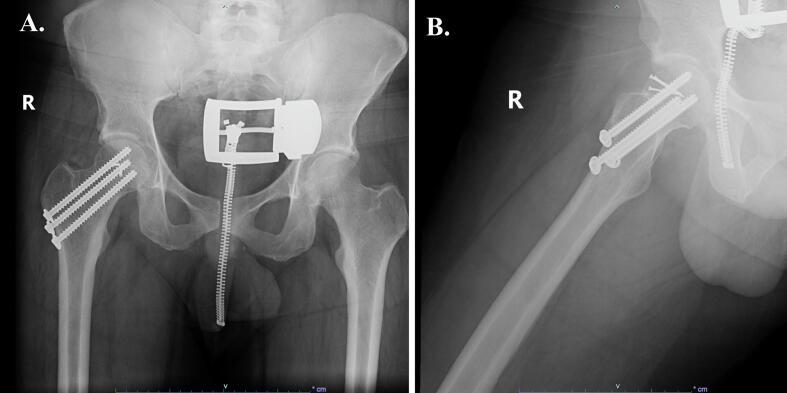

This clinical case report presents a 40-year-old male who sustained an ipsilateral hip and knee dislocation with ipsilateral femoral head fracture and incomplete femoral neck fracture following a motorcycle collision.

本临床病例报告介绍了一名40岁男性,该患者在摩托车碰撞后发生同侧髋部和膝部脱位,并伴有同侧股骨头骨折和股骨颈不完全骨折。